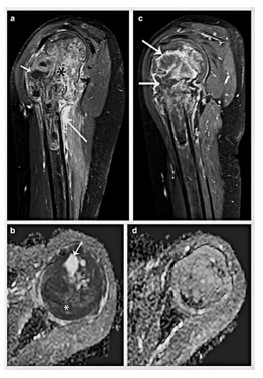

Sarcoma de Ewing.

Desde el punto de vista terapéutico, el tratamiento de estas neoplasias suele incluir una combinación de quimioterapia, cirugía y, en algunos casos, radioterapia. "El osteosarcoma convencional requiere dos ciclos de quimioterapia neoadyuvante antes de la cirugía, y la respuesta terapéutica se evalúa mediante el grado de quimionecrosis en los exámenes histopatológicos", indican en el estudio. En el caso del sarcoma de Ewing, la quimioterapia es fundamental, ya que "más del 90% de los pacientes presentan micrometástasis al momento del diagnóstico", apuntalan los investigadores.

Diagnóstico temprano

Uno de los aspectos más innovadores del estudio es su énfasis en la importancia de un diagnóstico temprano. "Reducir el tiempo transcurrido entre la aparición de los síntomas y el diagnóstico del sarcoma de Ewing y del osteosarcoma es fundamental para mejorar la supervivencia de los pacientes", afirman los autores. Entre los síntomas más frecuentes de estas dolencias se encuentran el dolor óseo persistente, la inflamación localizada y, en algunos casos, la fiebre o la pérdida de peso.